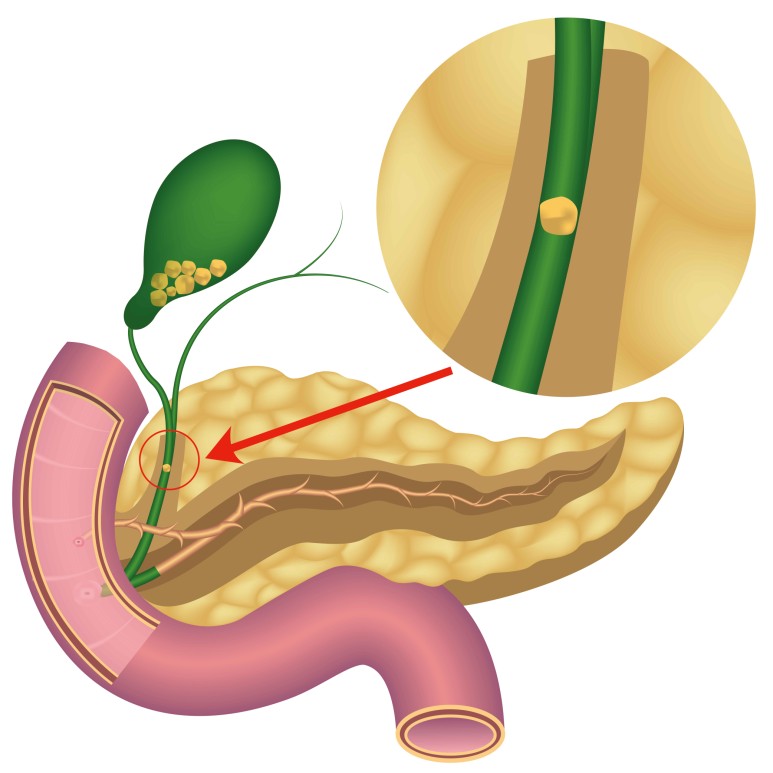

그 원인이 총 담관 담석의 경우 담낭 확장이 이루어지지 않는 경우가 많은데 이는 완전 폐쇄가 아닌 부분 폐쇄로 담즙이 부분적으로 흘러나와 담낭 내의 압력을 높이지 않기 때문입니다.

또한 총 담관 담석의 유래가 담낭인 경우에는 담낭에 만성적인 염증이 동반되어 섬유화가 진행되어 담낭의 확장이 불가능하기 때문입니다.

따라서 신체검진시 손으로 만질수록 담낭의 크기가 커지고 있으나 압통이 없는 경우에는

이를 Courvoisier 징후라고 하는데, 담관폐쇄의 원인이 총담관석에 의한 것이 아니라 악성폐쇄일 가능성이 높습니다.

담관폐쇄로 인해 담즙이 정체되어 있는 경우 세균증식이 자주 이루어지며 담관염이 발생합니다.담석으로 막혔을 때 흔히 발생하며 담석에 세균이 많이 분포되어 있어 부분적으로 폐쇄되는 경우 사이를 통해 세균이 담관 상부로 유입될 수 있기 때문입니다.